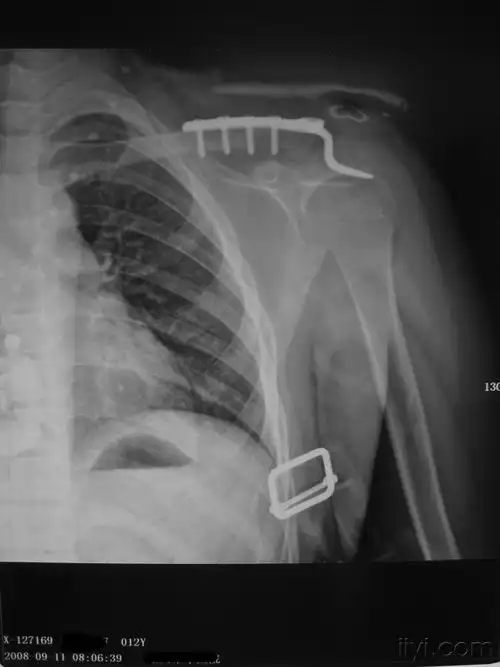

锁骨远端骨折经典术式

49岁锁骨粉碎性骨折切开复位锁定钢板系统内固定手术一例

患者双侧锁骨摄片

左肩锁关节脱位及复位后

锁骨骨折